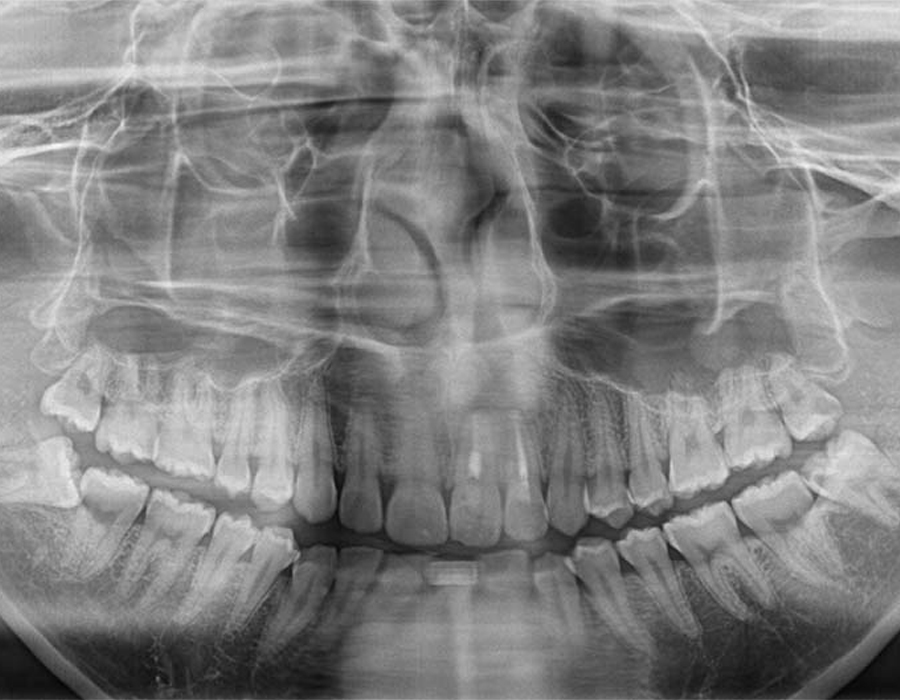

短時間で安全に親知らずを抜歯するためには、事前の画像検査が欠かせません。CT撮影により、親知らずや顎の骨の状態を詳しく知ることができます。その上でお口の中を拝見します。現状と歯科医としての意見をお伝えし、患者様と話し合いながら、抜歯を行うのか、残して経過観察に留めるか決定します。